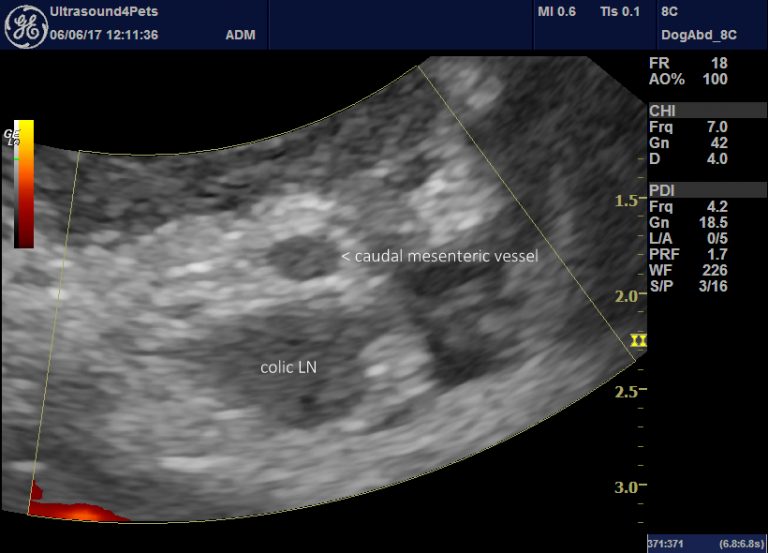

From northwestvetimage.com

Northwest Veterinary Imaging Dog Mesenteric Torsion Mesenteric torsion (mt) is a rotation of the intestines around the mesenteric axis causing luminal obstruction. Intestinal volvulus is a rare disorder in dogs in which there is rotation of a segment of the intestine on its mesenteric axis (gillespie et al.,. Mesenteric torsion is a pathological rotation of the intestinal tract around the axis of the mesenteric root, resulting. Dog Mesenteric Torsion.